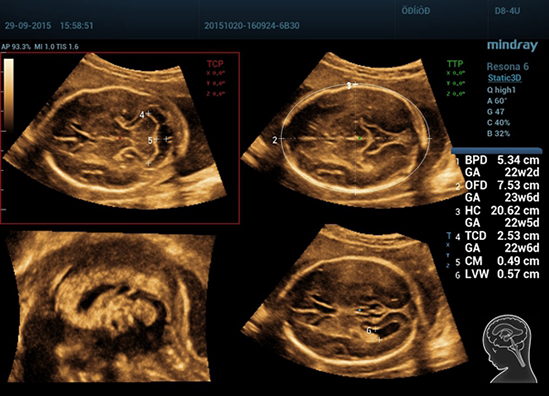

Клинические изображения Mindray Resona 6: